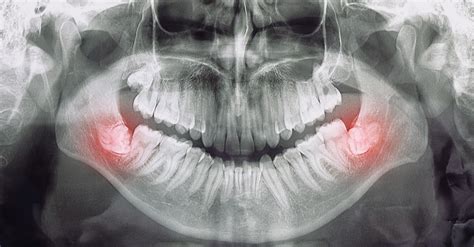

Muela del juicio retenida

Extracción de las Muelas del Juicio

La extracción de las muelas del juicio, o exodoncia de muelas, es una intervención quirúrgica común. En el caso de que la muela del juicio no tenga espacio para crecer (muela de juicio retenida) y provoque dolores intensos e incómodos, infecciones, u otros problemas dentales, es muy probable que sea necesaria su extracción.

Las muelas del juicio, también conocidas como terceros molares, son los últimos de los dientes permanentes de la boca en salir. Estas muelas tienden a salir entre los 17 y 25 años. El problema viene cuando las muelas del juicio no disponen de lugar suficiente en la boca para salir y desarrollarse normalmente.